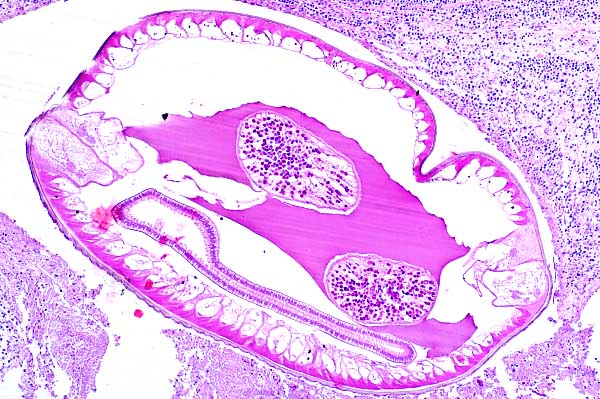

The nematode has a thick smooth pigmented cuticle (arrowhead), coelomyarian-polymyarian musculature (M), prominent and dissimilar lateral cords (C) and a pseudocoelom (P) containing small amounts of eosinophilic material.